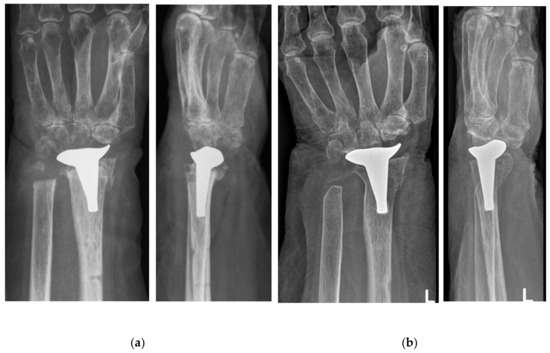

Wrist Hemiarthroplasty for Complex Intraarticular Distal Radius Fracture in a Patient with Manifest Osteoporosis

2. Case Presentation

| Parameters | Preint. | 1.5 Y | 6.5 Y |

|---|---|---|---|

| DASH | 86 | 5 | 38 |

| VAS for Pain | 7 | 1 | 0 |

| Flexion | 10° | 40° | 35° |

| Extension | 0° | 30° | 35° |

| Radialduction | 5° | 10° | 15° |

| Ulnarduction | 15° | 20° | 20° |

| Pronation | 30° | 90° | 90° |

| Supination | 40° | 90° | 90° |

| Grip Strength | - | - | 28 kg |

| Implant-Radius Angle | 6° | 8° | 8° |

| Implant-Styloid Distance | 35 mm | 36 mm | 37 mm |